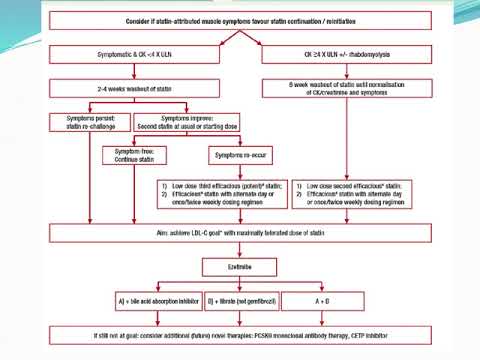

Síntomas musculares asociados a estatinas. Dr. Sebastián Ayuso. Residencia de Cardiología. Hospital C. Argerich. Buenos Aires